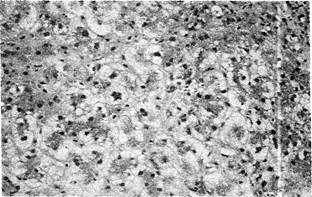

Исследование песочных ядер в гепатоцитах